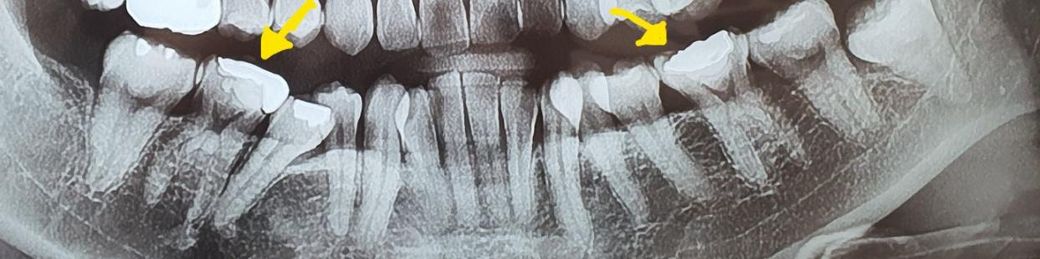

금으로 인레이되어있는 치아 크라운으로 재치료전에 엑스레이? ct로 신경치료해야하는지 알수있나요?

사진으로만 봤을 경우에는 치근단 질환이 있어 보이지는 않습니다. 특별한 통증이 없다면 굳이 CT를 촬영해야 할 필요는 없을것으로 생각됩니다.

엑스레이 상으로는 확인이 불가능하고 저상태에서는 직접 제거를 해봐야 알수 잇을것같습니다.

1. 인레이 치료 시 신경노출을 피하기 위해 기저재도 깔고 그랬지만 신경과 가까워 치수염이 유발되었을 수도 있고 비가역적인 치수염은 신경치료 합니다

2. 비가역적 치수염 상태는 꼭 ct로 판단하는것보다는 증상체크가 중요합니다

금 인레이가 되어 있는 치아의 정확한 진단을 위해선 추가적인 촬영이 필요할 수 있고 기간이 달라지진 않습니다.